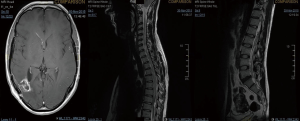

A 27-year-old gentleman presented with a 5-month history of tinnitus and increasing headaches in the occipital and orbital area. A CT scan was performed showing an intracerebral mass. An MRI head (Figure 1) was subsequently performed showing appearances consistent with a high-grade astroglial tumour with multifocal non-enhancing T2 hyperintense regions suggesting de-differentiation on a background of multifocal low-grade disease. Subtotal resection was performed and carmustine wafers were added to the surgical bed. Pathological tissue diagnosis was consistent with a right temporal lobe glioblastoma multiforme (GBM), IDH1 wild-type. The patient was treated with concurrent chemo-radiotherapy. In brief, intensity-modulated radiotherapy (IMRT) up to 60 Gy in 30 fractions to the right temporal lobe surgical bed with a margin and concurrent temozolomide (75 mg/m2/d × 7 d/week for 42 days). Five cycles of adjuvant temozolomide was given after chemo-radiation. The patient remained PS 0–1 during the treatment. Three weeks after finishing adjuvant temozolomide, the patient was admitted presenting left lower back pain, left lower limb heaviness and right lower limb sensory loss and numbness. At the time of admission neurological examination was normal except for sensory loss with a slightly impaired feeling in the lower right limb. The MRI of the brain showed mixed appearances, with response in the surgical bed but new foci in the corpus callosum and anterior periventricular region of the right hemisphere. The case was discussed at the Neuro Oncology Multidisciplinar Team meeting and advised to start second-line treatment with PCV (procarbazine, lomustine, and vincristine) was recommended. During this time, the patient had progressive neurological symptoms worsening with new leg weakness, unsteadiness, constipation, and difficulty passing urine. A spinal MRI (Figure 2) was performed showing multiple leptomeningeal and drop spinal metastases. The patient was treated with dexamethasone and underwent palliative radiation therapy to the thoracic and lumbosacral spine (from T12 to S3, 30 Gy in 10 fractions and from T5–T9, 20 Gy in 5 fractions). His clinical status continued to deteriorate declining and he was transferred to a palliative care service.

A 43-year-old lady with a past medical history of von Willebrand’s disease, had problems with double vision, nausea and headaches. An MRI of the brain (Figure 3) was performed showing a likely pontine low-grade glioma. Due her past medical history of von Willebrand’s disease and the location of the lesion a biopsy was not possible. The patient was treated with radiotherapy up to 54 Gy in 30 fractions to the visible tumour on MRI. The first follow-up MRI done 2 months after radiotherapy showed an increase in the size of the cystic component of the tumour with new multifocal solid nodular enhancement. Concluding remark stated that the MRI features most likely represented disease progression rather than radiotherapy-related changes. At the same time, the patient had been getting increasing problems with her vision in her left eye, weakness and numbness in her right side and has had a few falls. Neurological examination showed grade 3/5 power loss in her right arm and 4+/5 in her right leg. Because of the behaviour of high-grade glioma, salvage chemotherapy with temozolomide, six cycles every 28 days was planned. She started with dexamethasone as symptomatic treatment as well. During chemotherapy, the patient’s symptoms improved and allowed reduction of the steroids reduction. She completed six cycles of temozolomide and started follow-up with MRI. Eleven months after finishing salvage chemotherapy progressive disease was noted with a new enhancing lesion in the right posterior cerebellum and increase in size and enhancement of the left pontine lesion. Simultaneously, the patient started with slight right leg weakness and headaches at the right side. She started PCV as second-line chemotherapy. Unfortunately, PCV was stopped after two cycles due to neutropenic sepsis and worsening performance status. Six wee4ks later the patient was admitted to hospital with left leg weakness and urinary retention. A spinal MRI (Figure 4) was done, showing multiple cystic and solid intradural lesions in the lumbar spine causing nerve cauda equine compression. The patient was treated with dexamethasone and underwent palliative radiation therapy (8 Gy in single fraction) to the lumbar spine (T12–S5). She was transferred to a palliative care service.